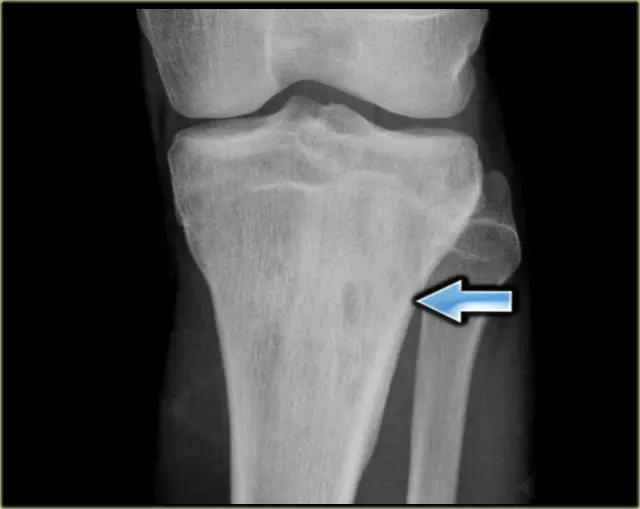

上图为胫骨近端干的边界欠清的骨性病变,具有广泛的反应性硬化和固体骨膜反应。